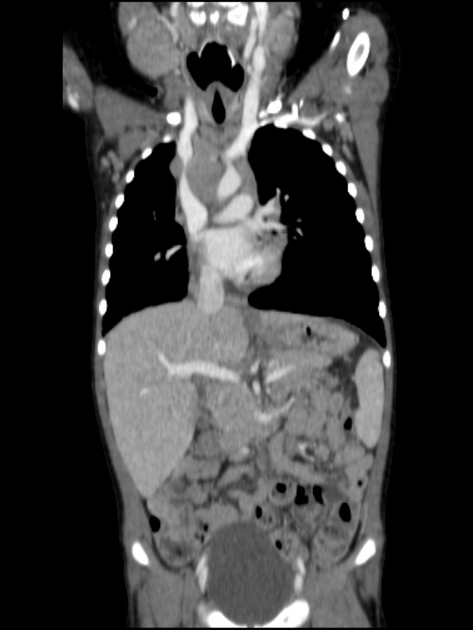

• Bệnh Erdheim-Chester (Erdheim-Chester Disease - ECD)